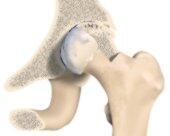

Die häufigste Ursache für die Implantation einer Hüftprothese (ca. 60% aller Fälle) stellt die Arthrose dar. Hierbei kommt es durch das Aufbrauchen der knorpeligen Auskleidung des Gelenkes im Spätstadium der Erkrankung zum unmittelbaren Knochenkontakt zwischen Hüftpfanne und Hüftkopf. Dies verursacht eine schmerzhafte Bewegungseinschränkung durch die entstehende Entzündungsreaktion, eine Schrumpfung des umgebenden Weichteilgewebes und die Bildung von knöchernen Randanbauten an den Gelenkpartnern (Osteophyten).

Bei den totalen Hüftendoprothesen (Hüft-TEP) werden in der Regel eine künstliche Hüftpfanne und eine Schaftprothese mit Aufsteckkopf implantiert. Hierfür stehen unterschiedliche Prothesenmodelle und Verankerungsmöglichkeiten (zementiert, zementfrei) zur Verfügung. Eine neuere operative Versorgungsmöglichkeit stellt der Hüftoberflächenersatz dar. Es handelt sich hierbei um ein besonders knochensparendes Prothesensystem, dessen klinischer Einsatz jedoch noch jung ist, sodaß potentielle Vorteile noch nicht abschließend beurteilt werden können.